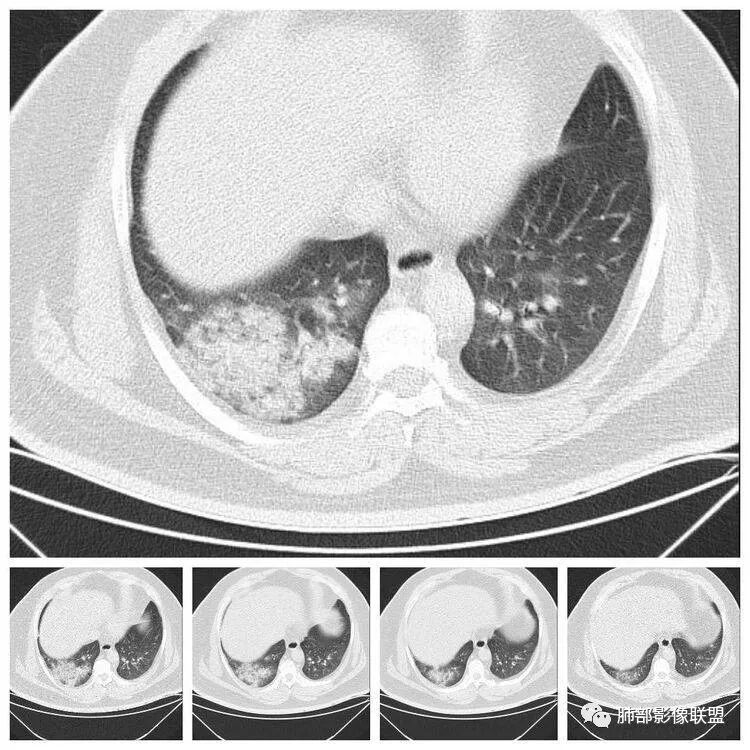

青年男性、急性病史、发热、咳嗽、常规抗炎无效病灶沿支气管血管束分布  GGO+实变边界模糊部分沿胸膜下分布哪几种可能?

南边:1、感染:间质分布——病毒、支原体,支原体一般树芽征明显,累及小气道多,而且临床轻,不太支持2、血管炎,需要相关病史3、肺水肿:心脏不大,无胸水、无中央间质增厚、小叶间隔增厚,不太支持4、PAP,病史影像表现都不支持初学者:可能是病毒,但是好像并不是我们常见的流感病毒实变为主,腺病毒?就是太多灶了一点

重症流感的定义出现以下情况之一者为重症病例1.持续高热>3天,伴有剧烈咳嗽,咳脓痰、血痰,或胸痛2.呼吸频率快,呼吸困难,口唇紫绀;3.神志改変:反应迟钝、嗜睡、躁动、惊厥等4.严重呕吐、腹泻,出现脱水表现;5.合并肺炎6.原有基础疾病明显加重。危重症流感的定义出现以下情况之一者为危重病例1.呼吸衰竭2.急性坏死性脑病3.脓毒性休克4.多脏器功能不全5.出现其他需进行监护治疗的严重临床情况。重症流感病毒肺炎的肺部影像以双肺多发磨玻璃影及实变影为主要表现,可合并少量胸腔积液,典型的H1N1双肺外带分布为主。随病程发展,部分患者出现实变及纤维化临床表现早期流感样症状:咳嗽、咳痰、发热、咽痛、全身酸痛。主要临床表现:肺炎、ARDS。患者咳嗽、咳痰、呼吸困难、氧饱和度低,发热、咽痛、全身酸痛,神志异常。甚至呼吸衰竭、休克,多器官衰竭等等。相关链接https://m.qlchat.com/topic/details?topicId=280000451285864

起病突然,高热,双肺多发磨玻璃影及实变影,胸膜下分布为主,不具有肺门分布优势,也没有小叶间隔增厚,一般会首先考虑病毒感染,尤其是甲流。